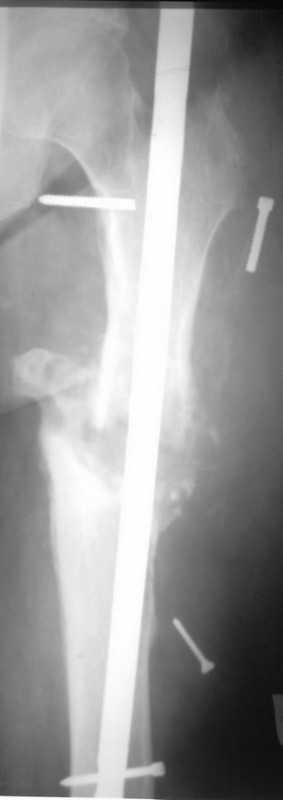

[Ortho] Псевдоартроз бедренной кости, инфекция.

Здравствуйте уважаемые коллеги, прошу Вашего мнения относительно тактики лечения пациента М. 37 лет, рост 170 см. вес 140 кг.

в 2007 году перелом фиксатора после чего обратился в нашу клинику, где было произведено удаление гвоздя, БИОС L-360 mm D-12 mm с кортико-спонгиозной пластикой, в теч. 6-и мес. больной был под наблюдением динамизация ч-з 2 мес. после чего пациент исчез с поля зрения.

Появился с жалобами на болезненность в месте перелома, укорочение ноги, в течении года поочередно в ягодичной области и н/3 бедра функционирующие свищи.

На данный момент имеем свищ в н\3 бедра, укорочение ноги на 3 см, внешняя ротация.Произведена фистулография, взят посев из свищевого хода.

Планируется:

- Удаление м\фиксатора и всех винтов(за исключением проксимального)

- I&D с рассверливанием до 16 мм.

- кортикотомия, открытое устранение деформаций

- БИОС стержнем L-360 mm D-12 mm с а.б. покрытием

- бусы с ванкомицином в области свищей